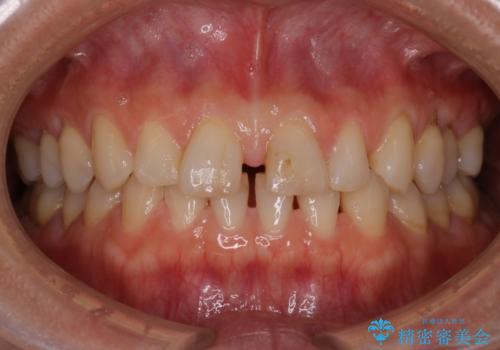

- 右上2番が欠損しており、歯並びをバランスよくしたいということで来院されました。

ワイヤー装置とマウスピースで悩まれていましたが、マウスピースで治療可能と判断致しましたのでマウスピースにて治療しました。

IPR、歯列弓拡大、ゴム掛けを行い歯並びを整える治療計画を立てました。

右上2番が欠損しているため、見た目と噛み合わせの両方のバランスを整えるために経過を追いながら必要な部位にゴム掛けをしました。

最終的に、見た目も噛み合わせも患者様に満足いただけました。